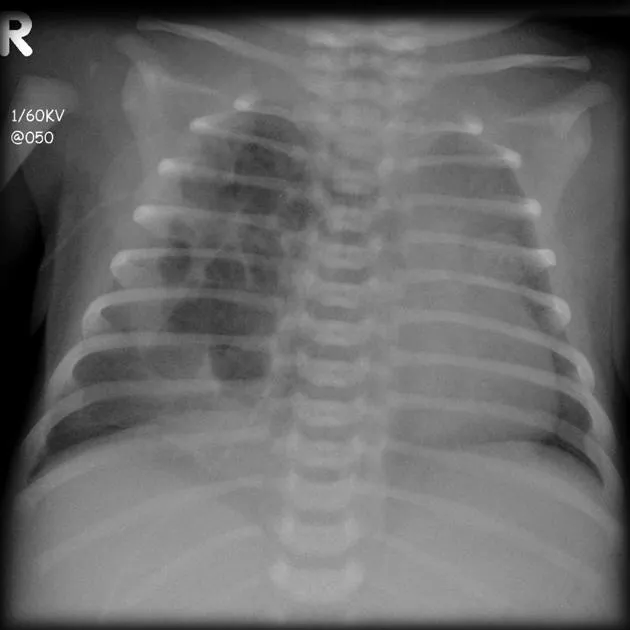

Congenital Lobar Emphysema (CLE):

- Progressive overdistension of lobe(s); LUL > RML > RUL.

- Cause: Bronchial check-valve (cartilage defect).

- Symptoms: Neonatal respiratory distress, wheezing.

- CXR: Hyperlucent lobe, mediastinal shift, compressed lung.